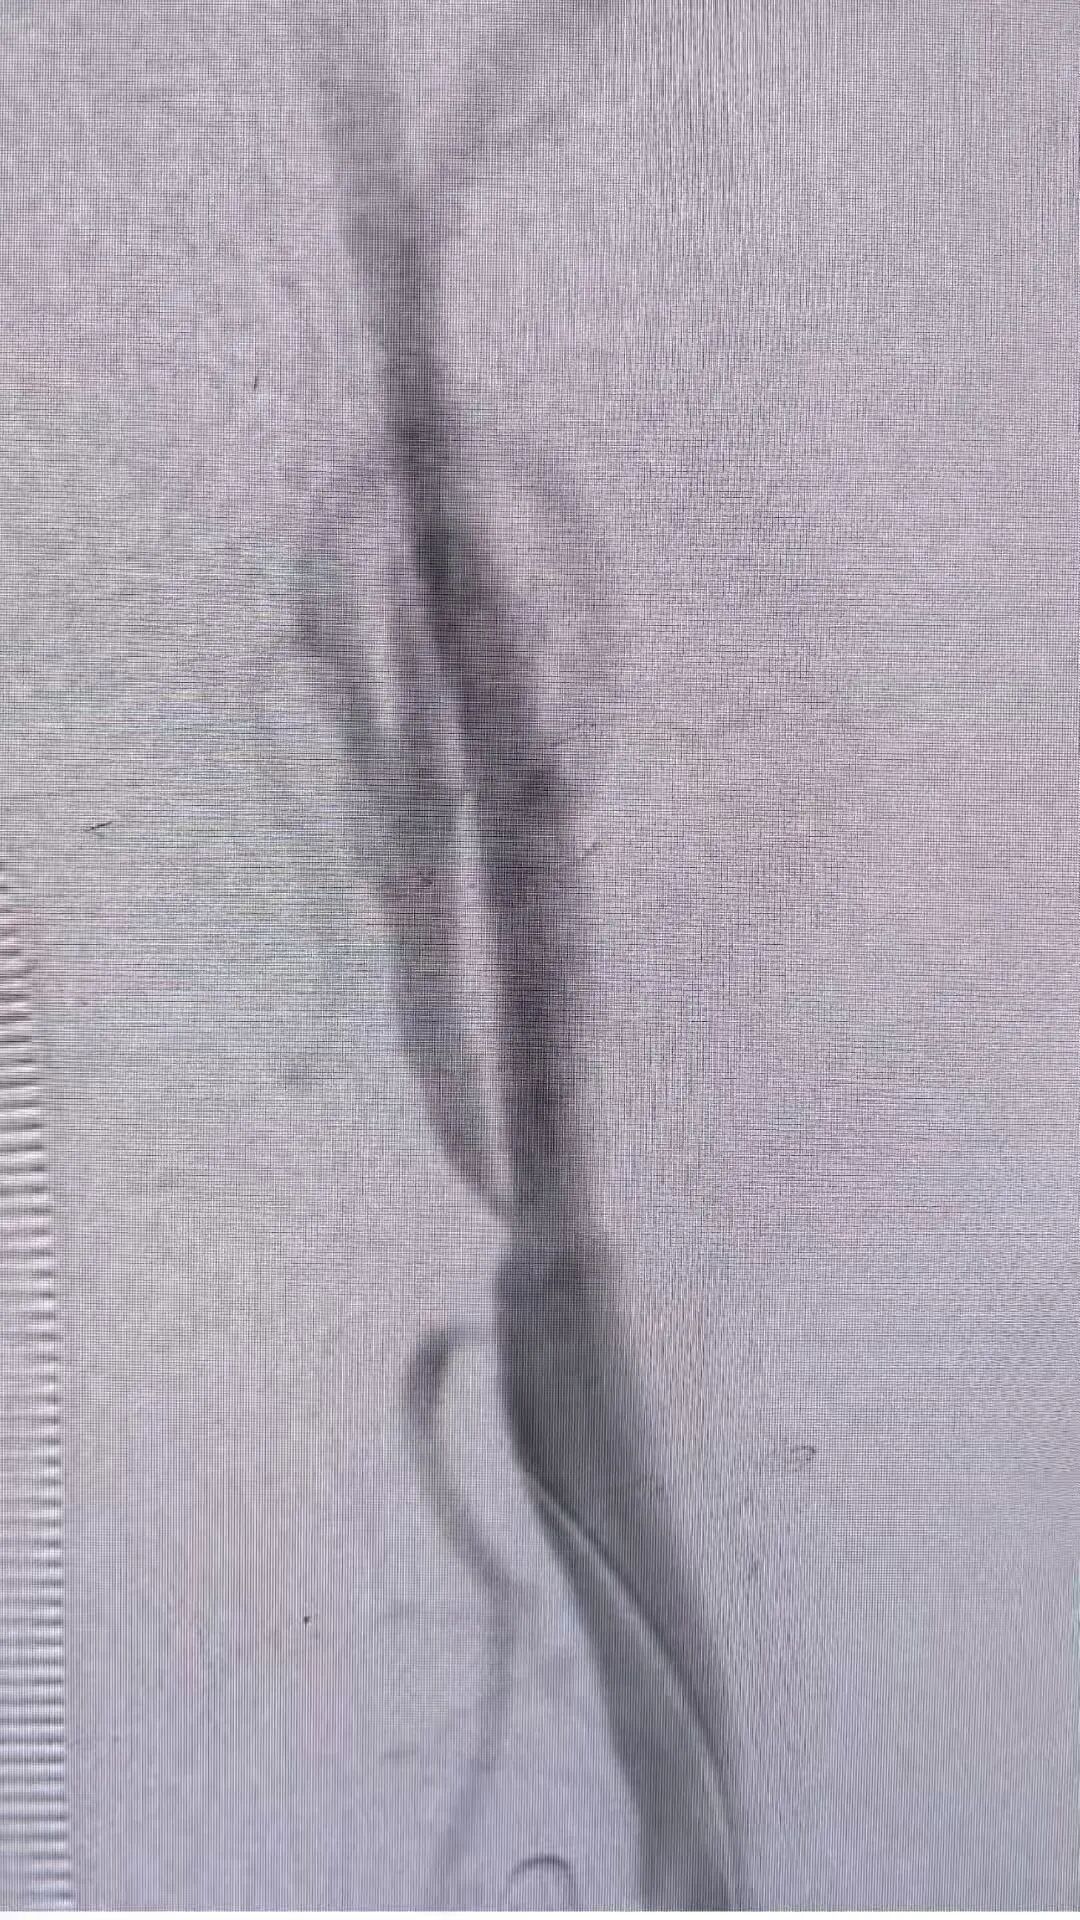

术前及术后造影图像:

本次手术由我院心脏血管外科核心团队主导,术前联合麻醉科、影像科等多学科进行全面评估,制定个性化手术方案;由兴安盟人民医院特聘教授刘鹏、兴安盟人民医院副院长周智勇主刀,术中团队密切配合,精准操作每一步,历时1.5小时顺利完成,术后患者生命体征平稳,无并发症发生,目前已顺利康复。